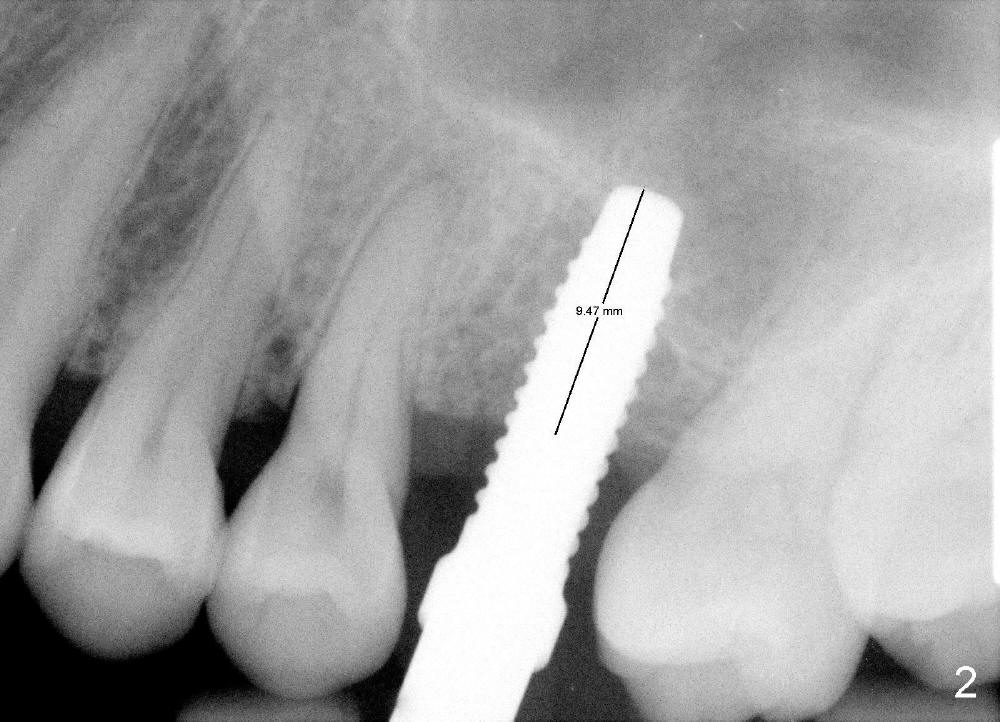

After local anestheisa, an incision is made. The initial osteotomy at the site of the upper left 1st molar is created by 1.6 mm pilot drill at the depth of 6 mm (Fig.1), followed by insertion of bone expanders 2.6, 3.0, and 3.4 mm at approximately 7, 8, and 9 mm deep (Fig.2). A 4.1 mm bone tap is inserted approximately 10 mm without much binding. Mineralized allograft mixed with Osteogen is used for sinus lift. A 4.5x12 mm implant is placed with insertion torque around 35 Ncm (Fig.3). A 5.2 mm healing abutment is placed. The flaps are sutured. The wound is covered by perio dressing.